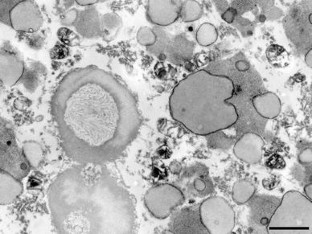

Recently, sporadic amyotrophic lateral sclerosis (SALS), a fatal neurological disease, has been shown to be a multisystem proteinopathy of TDP-43 in which both neurons and glial cells in the central nervous system are widely affected. In general, the natural history of SALS is short (<5 years). However, it is also known that a few patients may survive for 10 years or more, even without artificial respiratory support (ARS). In the present study using TDP-43 immunohistochemistry, we examined various regions of the nervous system in six patients with SALS of long duration (10–20 years) without ARS, in whom lower motor-predominant disease with Bunina bodies and ubiquitinated inclusions (UIs) in the affected lower motor neurons was confirmed. One case also showed UIs in the hippocampal dentate granule cells (UDG). In all cases, except one with UDG, the occurrence of TDP-43-immunoreactive (ir) neuronal cytoplasmic inclusions (NCIs) was confined to a few regions in the spinal cord and brainstem, including the anterior horns. In one case with UDG, TDP-43-ir NCIs were also detected in the substantia nigra, and some regions of the cerebrum, including the hippocampal dentate gyrus (granule cells). The number of neurons displaying NCIs in each region was very small (1–3 per region, except the dentate gyrus). On the other hand, the occurrence of TDP-43-ir glial cytoplasmic inclusions (GCIs) was more widespread in the central nervous system, including the cerebral white matter. Again, however, the number of glial cells displaying GCIs in each region was very small (1–3 per region). In conclusion, compared to the usual form of SALS, TDP-43 pathology shown in SALS of long duration was apparently mild in degree and limited in distribution, corresponding to the relatively benign clinical courses observed. It is now apparent that SALS of long duration is actually part of a TDP-43 proteinopathy spectrum.